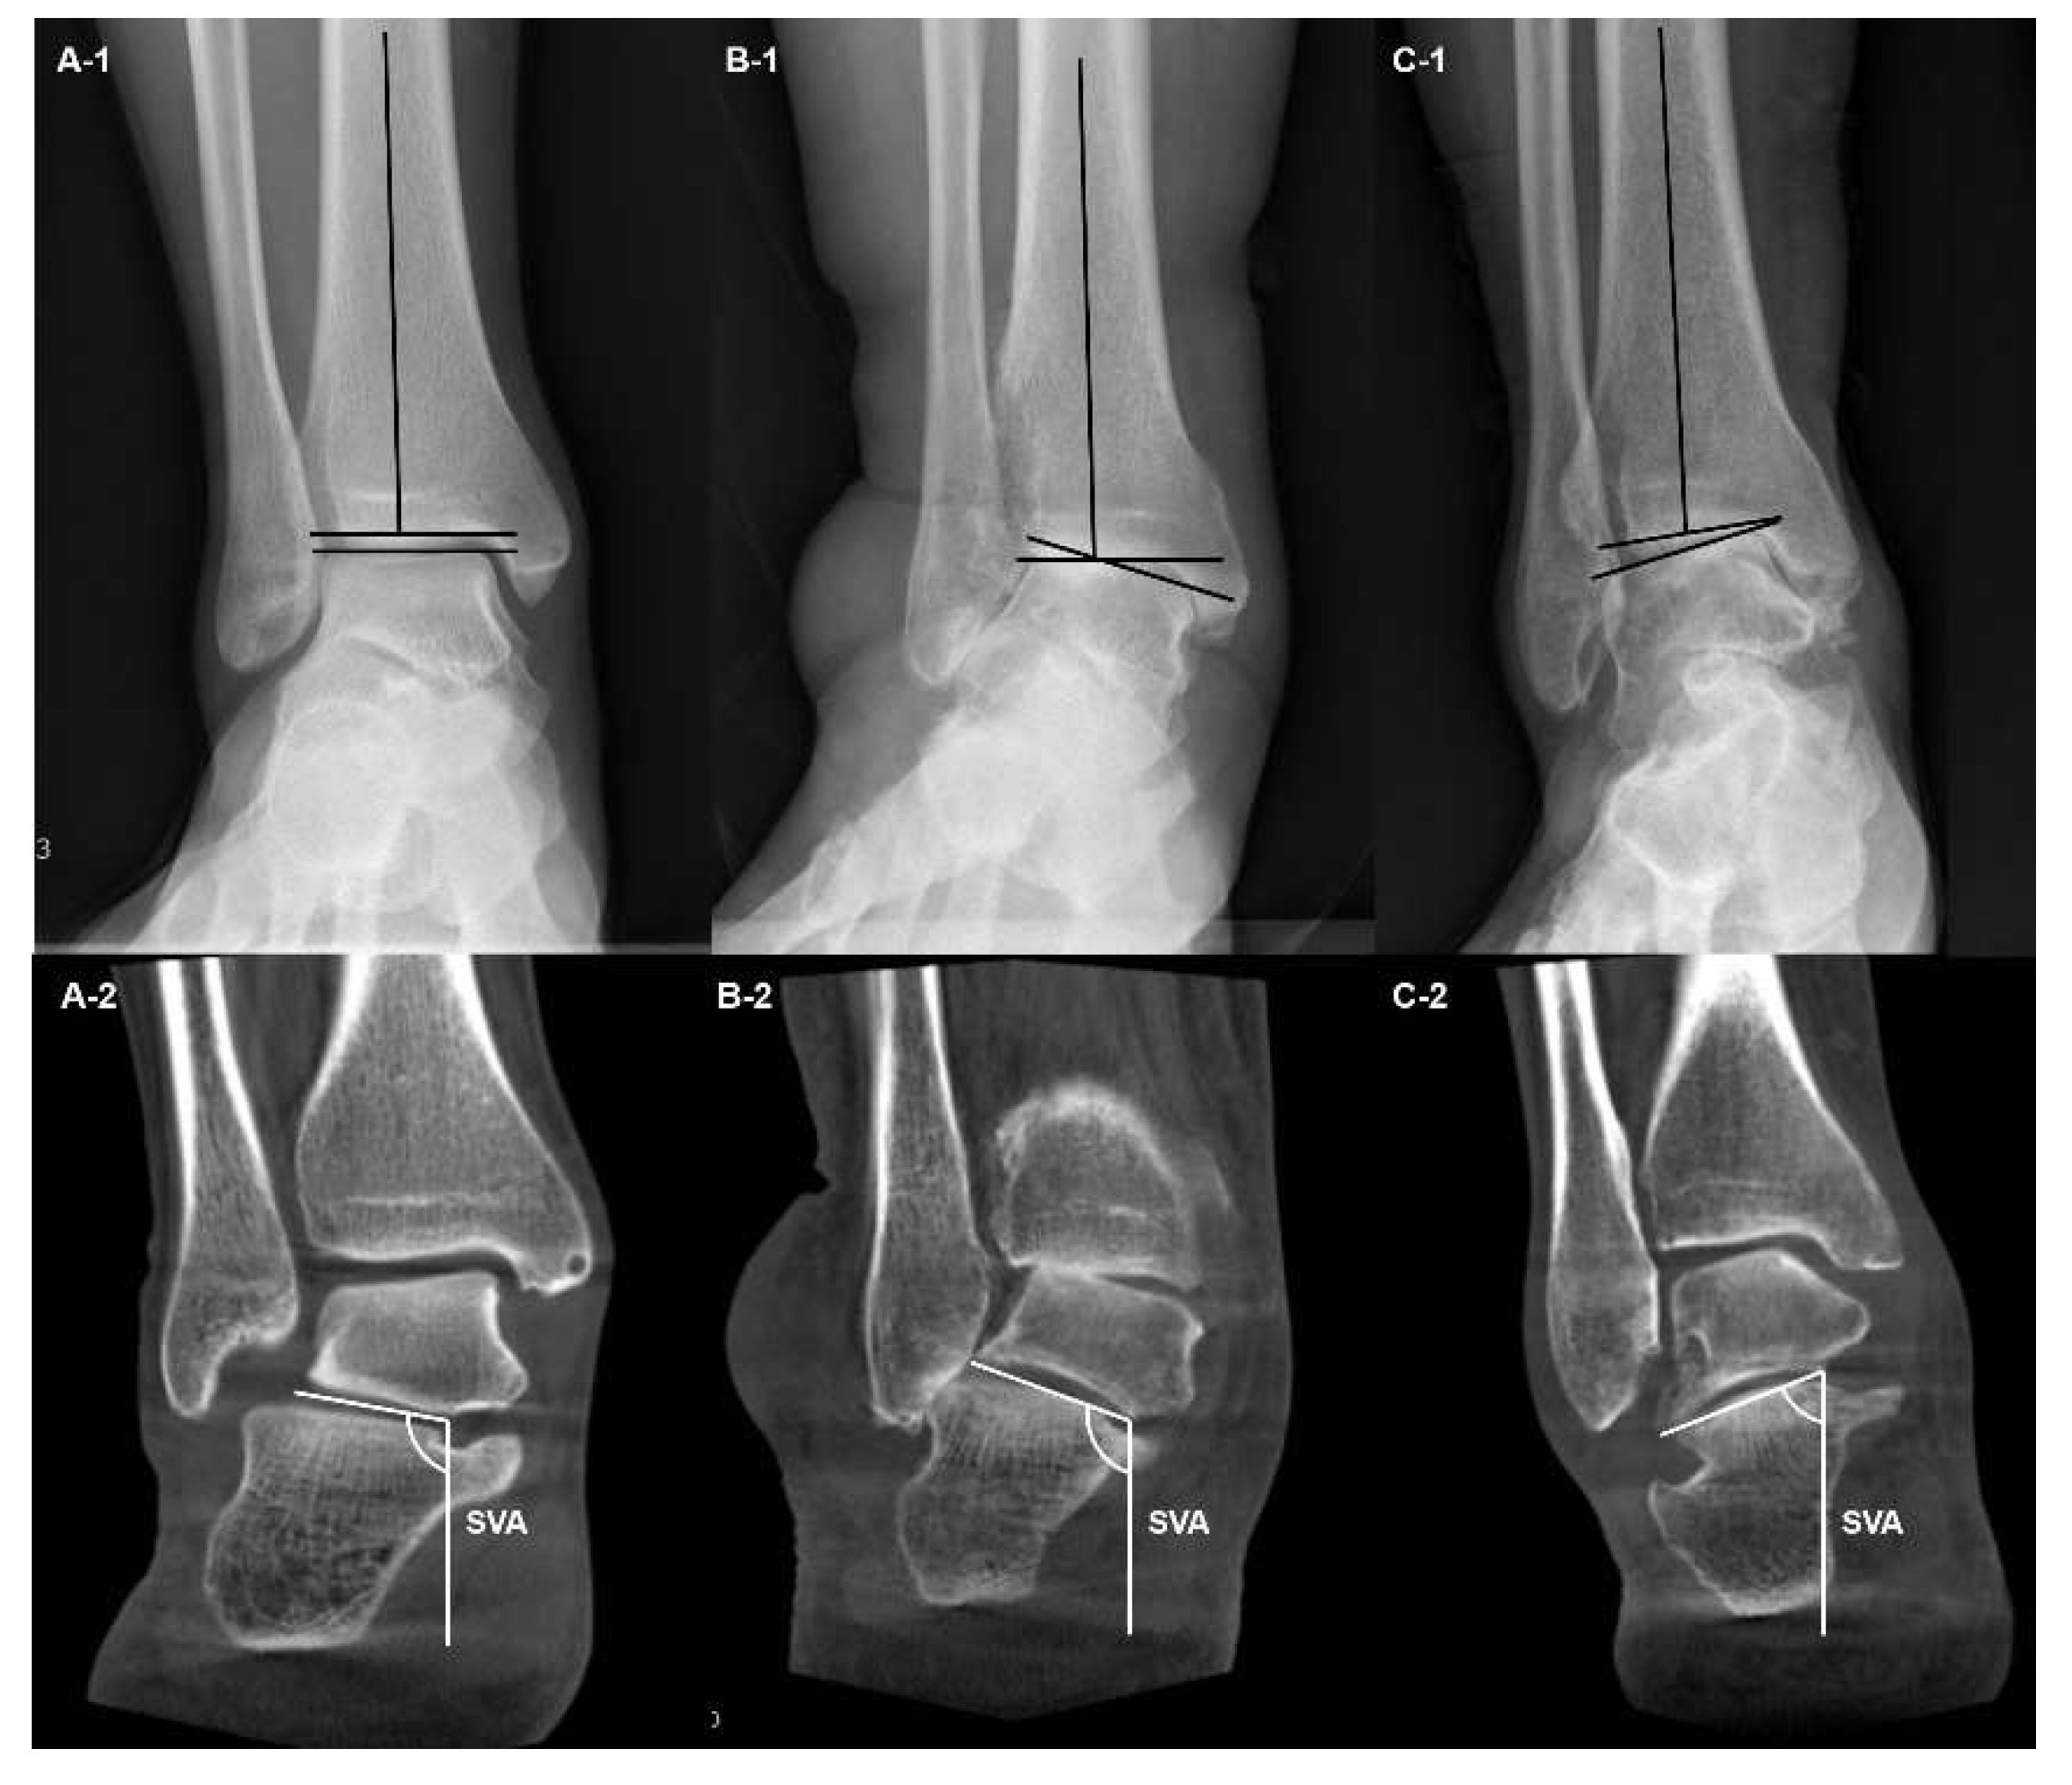

Using the WBCT, Richter et al proposed a classification, which subdivided ankle OA into four degrees [21]. The first-degree ankle OA includes joint space narrowing, which is not a complete loss, and osteophyte formation (Figure 4A). The second degree includes a partial or total loss of joint space (Figure 4B). The third degree implies presence of additional subchondral cysts with remaining joint surface congruence (Figure 4C). The fourth degree includes additional joint destruction with incongruity of the articular surface (Figure 4D). Authors commented that the new classification may effectively combine the classic features of osteoarthritis (joint space narrowing, osteophyte formation, and subchondral cysts) along with 3D visualization.

Figure 4. A classification system proposed by Richter et al. [21] (A) First degree of osteoarthritis with osteophyte formation and joint space narrowing, but not complete loss (B) Second degree of osteoarthritis with partial or complete loss of joint space. (C) Third degree of osteoarthritis with additional subchondral cysts, with remaining joint surface congruency. (D) Fourth degree of osteoarthritis with aggravated joint surface destruction and incongruence.